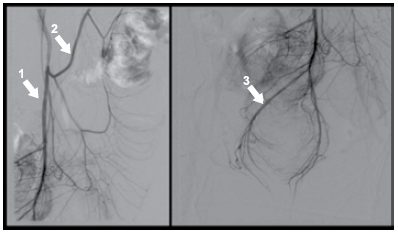

Na angiografia apresentada, assinale a alternativa que apresenta a correspondência respectiva das artérias apontadas.